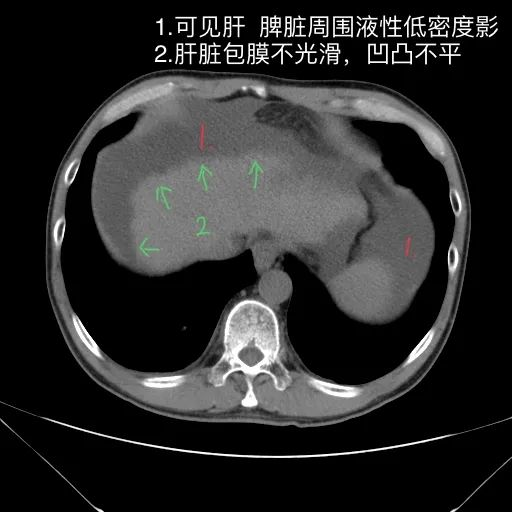

如上是肝硬化失代偿的典型表现。但没有门脉增宽和脾大表现。此外肝S4的小片低密度影除考虑为囊肿或镰旁假病灶外,还需警惕肿瘤?

肝脏缩小,包膜凹凸不平,肝裂增宽,各叶比例失衡,肝实质密度不均,肝S4小片低密度影,约cm;胆囊不大,其内未见异常密度影,胆道系统未见扩张;胰腺、脾脏形态、密度、大小未见异常;双肾上腺及双肾形态、密度、大小未见异常,双输尿管未见扩张,膀胱充盈良好,壁光滑,其内未见异常密度影;前列腺未见异常;胃肠道未见充盈,壁未见明确增厚,食管胃底多发迂曲、增粗血管,腹部及腹膜后未见肿大淋巴结;腹水。

1.肝硬化失代偿表现(腹水,食管胃底静脉曲张)。